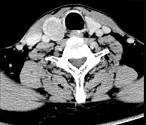

问题 男,43岁,因右颈部扪及一包块来院就诊。如图所示该患者应诊断为 ( )

选项 A、甲状腺原发淋巴瘤 B、甲状腺转移瘤 C、甲状腺腺癌 D、结节性甲状腺肿 E、甲状腺腺瘤

答案 E